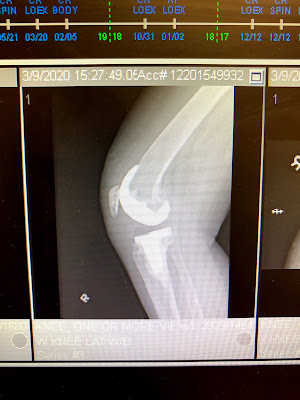

Per them: X-rays look perfect. Surgery scar looks perfect. Pain is very minor today.

Front of knee. They replaced the ends of my bones with surfaces made of chrome, titanium, and something, cemented in place, then put a pad in between to replace the cartilage that hasn’t been there for a very long time.

Some kind of plasticky stuff.

Side: and, yes, that’s my original patella hanging out at the front of my knee.